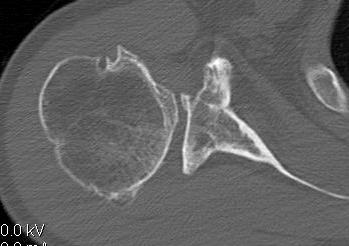

Hardware issues

Screw backout

Intra-articular screw

Graft malposition

Screws and graft too medial

Bone graft too medial

Nonunion with failure of fixation / recurrent instability

Nonunion with failure of fixation

Latarjet nonunion with hardware failure and displacement of coracoid fragment